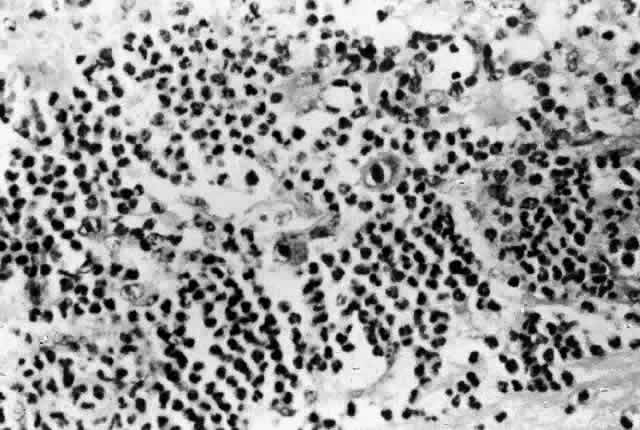

Cytomegalovirus (CMV) retinopathy is by far the most common of the severe ophthalmic infections in patients with AIDS. Varicella zoster virus retinopathy is being seen with increasing frequency; although it is probably the second most common retinal infection in North American HIV-infected patients, it is still far less common than CMV retinopathy. Toxoplasmic retinochoroiditis is the third retinal infection that is seen with some regularity, especially in certain areas of Europe and South America. The remaining retinal infections associated with AIDS are uncommon. They are seen with disseminated infections, in which the massive proliferation of organisms may overwhelm the patient's limited immune defenses. They are usually seen late in the course of the syndrome; thus, they may actually signal further waning of immune defenses. Patients with intraocular infections should be suspected of having tissue-invasive infections involving other internal organs. When they do occur, intraocular infections are frequently extensive and severe. Infections of the cornea and external eye are less common in HIV-infected individuals than intraocular infections. The natural defenses of normal eyelid function, tear film, and an intact corneal epithelium protect against many exogenous pathogens. It is therefore important that factors that might compromise those defenses, such as epithelial defects or trichiasis, be corrected as soon as possible. Also, HIV-infected patients who wear contact lenses should adhere strictly to lens care and disinfection techniques. Many HIV-infected individuals appear to have decreased aqueous tear production, which leads to feelings of dryness and irritation but does not seem to result in an increased incidence of ocular surface infections. At greater risk are patients who have permanent damage to the eyelids from zoster ophthalmicus, neurotrophic corneas from herpetic infections, or damage to the ocular surface from cicatricial conjunctivitis, similar to that of Stevens-Johnson syndrome, which is seen occasionally in patients with AIDS. HIV infection and its sequelae are being studied in a variety of animal models. Rhesus monkeys infected with simian immunodeficiency virus develop an AIDS-like illness. In this model the monkeys develop a variety of ophthalmic lesions, including CMV infections of the retina.10 This model may be useful for future studies of AIDS-related ophthalmic infections. CYTOMEGALOVIRUS Cytomegalovirus retinopathy is the most thoroughly studied of the ophthalmic manifestations of HIV infection. CMV retinopathy is an AIDS-defining index disease. Most studies have concentrated on treatment, but a great deal has been learned about the natural history of CMV retinopathy during the course of these studies. Cytomegalovirus is a ubiquitous DNA virus of the herpes group. Most of the adult population has been infected with CMV, but in most cases it does not cause any clinically apparent disease. The virus remains in the body, however, as a latent infection. In patients with AIDS, CMV can cause life-threatening infections involving many tissues, including the brain, lungs, and gastrointestinal tract. The reported prevalence of CMV retinopathy varies from 4% of ambulatory patients (primarily intravenous drug abusers)11 to 34% of eyes in an autopsy series of male homosexuals.9 This discrepancy may reflect the fact that CMV retinopathy occurs late in the course of AIDS. Most investigators believe that the true prevalence of CMV retinopathy among patients with AIDS is approximately 15% to 25%. It has been suggested that CMV retinopathy is more common in homosexuals, because of different levels of exposure to CMV between risk groups.11,12 Cytomegalovirus retinopathy is clearly a disorder of immunosuppressed persons. Prior to its association with AIDS, the infection in adults was seen almost exclusively in patients with defects in cellular immunity related to disease or immunosuppressive drugs.13,14 A single report of CMV retinopathy in a healthy adult was not confirmed by culture or tissue examination.15 There is no obvious correlation between the development of CMV retinopathy and levels of CMV antibodies. CMV retinopathy has been reported in the absence of detectable antibodies.16 Histologic studies of AIDS-related CMV retinopathy demonstrate the tissue necrosis and cytomegalic cells characteristic of all CMV infections (Fig. 1).9,17 Electron-microscopic and immunochemical studies have identified CMV viral particles and antigen in a patchy distribution throughout all layers of the retina and occasionally in contiguous retinal pigment epithelial cells.9 Viral antigens are only rarely identified in the choroid.9,18 Viral antigen in the choroid has been found in association with vessels and is not always adjacent to areas of retinopathy, suggesting that the virus reaches the choroid through independent hematogenous spread rather than by extension of infection from the retina. Among cases of AIDS examined at autopsy, 22% to 50% of those with CMV retinopathy have neutrophilic infiltrates in retinal tissue.9,19 This finding is atypical when compared with CMV retinopathy in non-AIDS patients, in which only a sparse lymphocytic infiltrate is observed. The difference has been attributed to intact granulocyte function and chemotaxis in patients with AIDS, in contrast to infants, organ transplant recipients, and patients with malignancies who can have more severe quantitative or qualitative granulocyte dysfunction.9 It has been noted that patients on immunosuppressive drugs can develop marked inflammatory reactions to CMV retinopathy when such drugs are withdrawn.14 Acute inflammatory cells may extend into the adjacent choroid despite the absence of identifiable viral antigens.9 The vitreous usually remains remarkably free of inflammatory material, despite the presence of virus in the vitreous cavity.20 A variety of stimuli (CMV antigen, immune complex deposition, and tissue necrosis) may be responsible for the production of chemotactic factors leading to neutrophilic infiltration. Immunochemical studies have revealed deposition of IgG, IgA, and, to a lesser extent, IgM and C3c in retinal tissue and within retinal arteriolar walls.9 Many IgA-bearing plasma cells were present in one case.17 Perivascular infiltration of neutrophils occurs, consistent with immune complex-mediated vasculitis,9,17 but there is poor correlation between the distribution of tissue-bound immunoglobulins, acute inflammatory cells, and CMV antigens.9 Thus, it is also possible that concurrent retinal infection with other as-yet-unidentified pathogens is responsible for the acute inflammatory reaction seen in these eyes. Inflammatory cell products do not appear to play a significant role in the extensive tissue destruction common to all cases of CMV retinopathy. The histopathologic characteristics of AIDS-related CMV retinopathy in one autopsy study are listed in Table 3.9 CMV retinopathy frequently begins adjacent to retinal vessels in the posterior pole (Fig. 2). It is believed that virus reaches the eye via the bloodstream. Untreated CMV retinopathy in patients with AIDS is a relentlessly progressive disease. Usually, infection begins with an isolated focus of disease; rarely are there more than two or three discrete areas of infection within the eye. These lesions invariably enlarge to involve additional retinal tissue. New lesions develop less frequently. The enlargement of lesions does not progress at the same rate from all lesion borders.21 The rate of progression is faster in an anterior direction toward the ora serrata than in a posterior direction toward the fovea. CMV retinopathy has been considered a “foveal-sparing” disease. In a series of organ transplant patients with CMV retinopathy reported by Egbert and associates prior to the AIDS epidemic, only 3 of 21 eyes had macular involvement.14 The higher incidence of macular involvement in early autopsy series of patients with AIDS may reflect the fact that progression of CMV retinopathy into the macular region could not be stopped prior to the introduction of ganciclovir and foscarnet therapy. Even though the fovea can eventually be destroyed, it is usually the last area to become infected; in some cases the disease appears to move circumferentially around the fovea (Fig. 3). Eventually the entire retina will be destroyed, usually within a 6-month period.19 Progression of the retinopathy halts abruptly at the ora serrata.9 Following total retinal necrosis, it is replaced by a thin gliotic membrane.19 No virus can be identified in ocular tissue at this late stage.